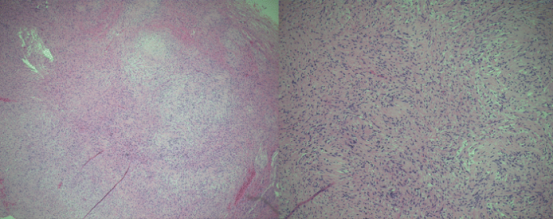

苏木精- 伊红染色的组织学标本显示细胞区域含栅栏状排列的细胞核(安托尼 A 型),交替出现少细胞区域由疏松水肿间质中不规则排列的细胞构成(安托尼 B 型)。